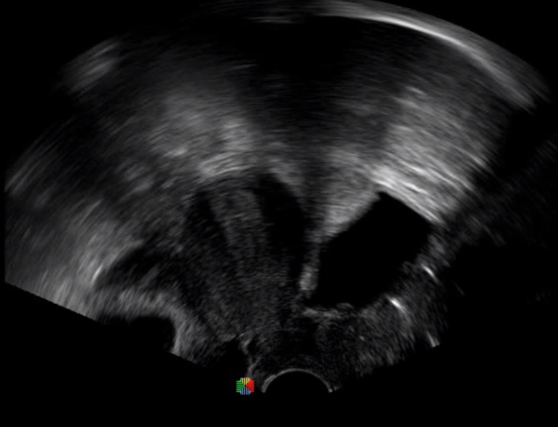

多數(shù)的生殖科醫(yī)生對于受精卵的植入采用憑經(jīng)驗操作或是使用傳統(tǒng)腔內探頭引導,同樣存在手術空間小、受精卵放置位置不確定等風險。專業(yè)的宮腔專用探頭,配合專用的窺器使用,為醫(yī)生提供最大的手術視野。

胎移植臨床圖